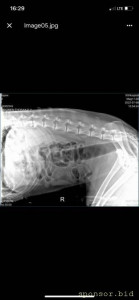

08.07.2022 г. передо мной на Варшавском шоссе сбили собаку, человек совершивший наезд даже не остановился и укатил дальше, я выбежала из машины, смогла остановить движение пары соседних полос, чтобы пес мог отползти на траву ( поднять и перенести не представлялось возможным, т.к. мне нельзя поднимать более 2 кг, более того непонятно что могла сделать собака в состоянии стресса и шока), после чего нашла парковку для машины и побежала к собаке, благо на тот момент несколько неравнодушных людей уже окружили его (это мальчик). Нами была вызвана полиция, составлено заявление ( но, думаем вряд ли кто-то будет этим заниматься.. так же сделан запрос в московскую службу видеофиксации, чтобы был сделан архив видео, если там есть камеры (тогда было не до этого, чтобы рассматривать есть ли они там), и в последствии приобщить к делу, или хотя бы найти того козла). Договорились со службой отлова, чтобы они на своей газели помогли довезти собаку до клиники шанс био, т.к. непонятно было что у нее с лапами, в клинике сделали рентген, несколько капельниц, обработали рану (т.к. задняя лапа разодрана до кости), взяли анализы, вкололи обезболивающие и отпустили.. т.к. у них нет стационара для бездомных, а так же хирурга, который мог бы сделать операцию. по заключению - кровоизлияние в глаз, открытая рана на левой заплюсне, вывих левого тбс (но вправить его нельзя, нужно делать операцию) порваны связки. по сумме в клинике оставили 14 500 руб. далее собаку отвезли в стационар надежда, с пятницы по воскресенье - обошлось в 10 552 руб (сам стационар, плюс лекарства, уколы и обработка ран, консервы, но он не ел). сегодня собаку возили на консультацию к хирургу в клинику беланта, было сделано дополнительно узи, на данный момент необходимо стабилизировать собаку, т.к. она еще в состоянии шока и с пятницы даже не ела, сейчас его опять повезли в стационар, необходимо еще делать уколы и обрабатывать рану, так же необходимо сделать 2 операции: на бедро (27200) и колено(55000), чтобы он смог передвигаться. в клинике заплатили 8167 с учетом лекарств. завтра планируется прием е еще одному хирургу в добрые руки, там по телефону озвучили цены на операции ниже чем в беланте, но нужен осмотр хирурга и его заключение. итого на данный момент на собачку ушло 33 219 руб. просим в сложившейся ситуации финансово помочь в судьбе пса, возможно найти ему любящих хозяев, на улицу его выкинуть уже просто невозможно, он там погибнет.. пес безумно умный, терпеливый, добрый, за все время ни разу не пытался агрессировать, укусить или что-то еще..

рентген

Помощь сбитой собачке - рентген 6.jpeg

Помощь сбитой собачке - рентген 1.jpeg

Помощь сбитой собачке - рентген 2.jpeg

Помощь сбитой собачке - рентген 3.jpeg

Помощь сбитой собачке - рентген 4.jpeg

Помощь сбитой собачке - рентген 5.jpeg